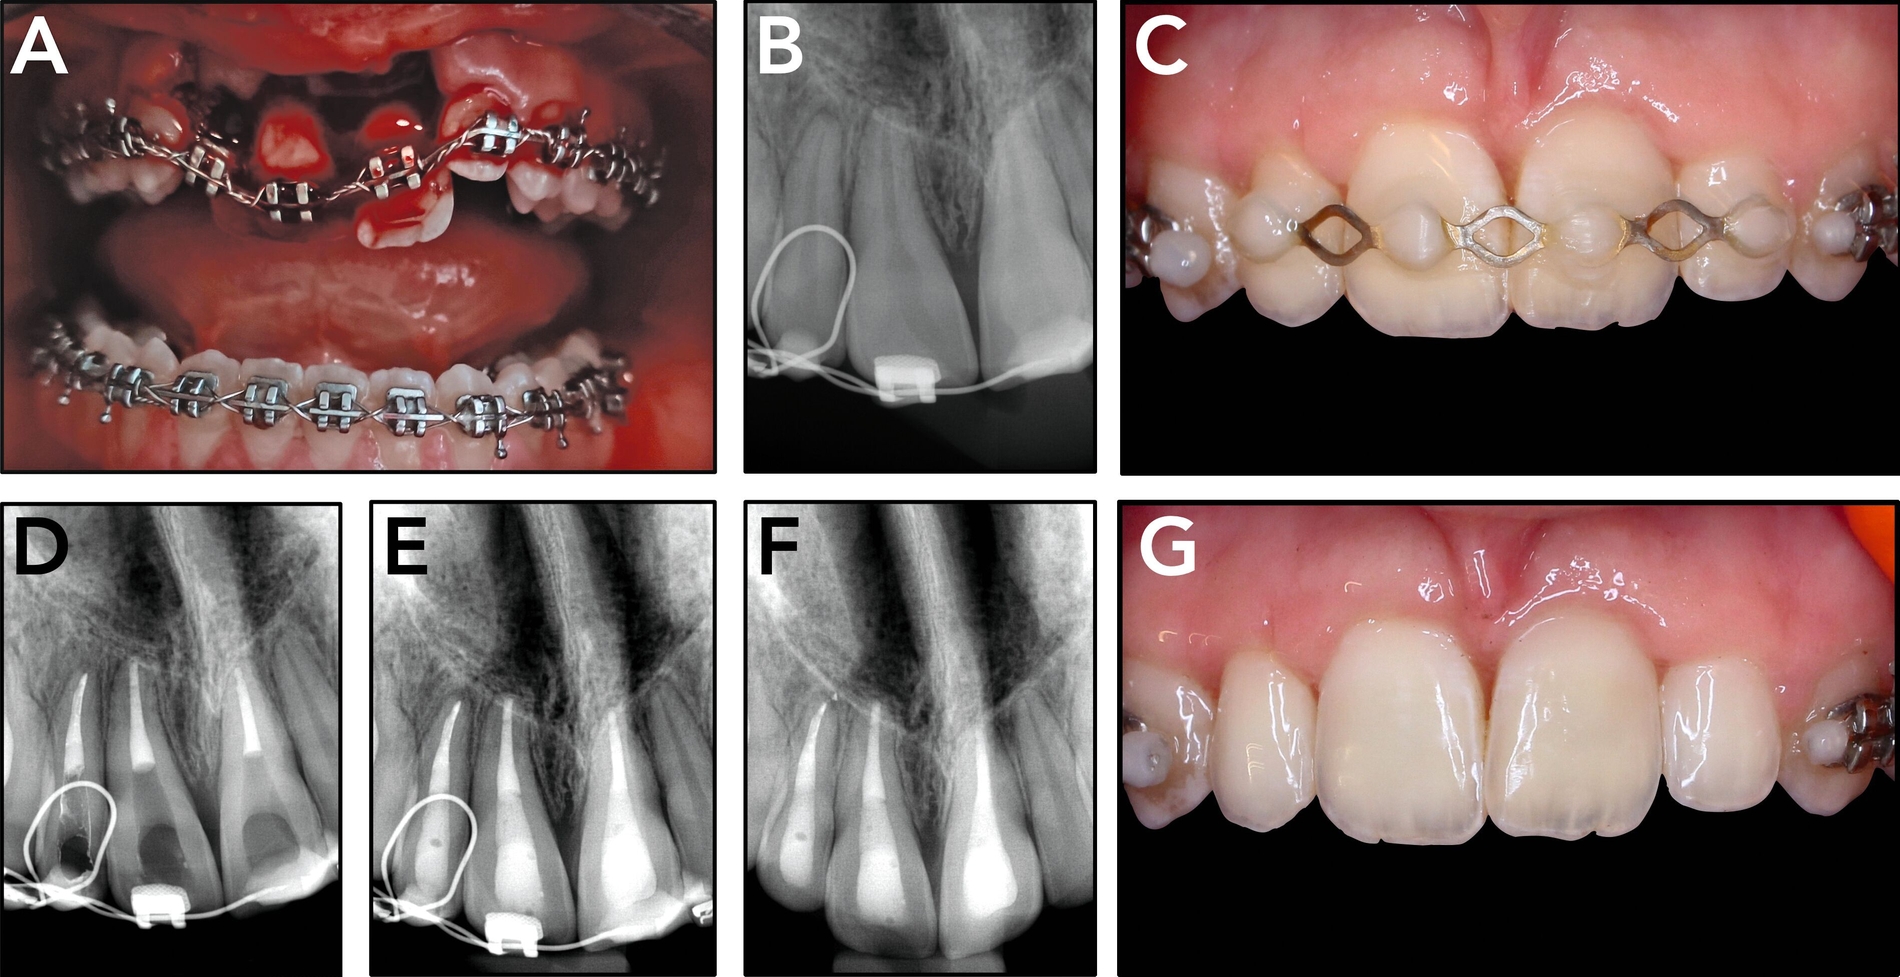

Eine Dekoronation ist eine chirurgische Intervention, die durchgeführt werden kann, wenn aufgrund ausgeprägter Schädigungen der desmodontalen Zellen und der Wurzeloberfläche eine Resorption auftritt. Im Rahmen der klinischen Untersuchung imponiert der betroffene Zahn aufgrund der Ankylose mit einem metallischen (hellen) Klopfschall. Röntgenologisch lassen sich Resorptionslakunen an der Wurzeloberfläche erkennen. Bei progressiver Resorption und Infraposition des betroffenen Zahnes in Relation zur Restdentition kann eine Dekoronation indiziert sein [Malmgren et al., 2015] (Abbildung 2).

Das Ziel der Dekoronation ist es, die klinische Krone unter Belassung der resorbierenden Wurzel zu entfernen, damit der Alveolarknochen aufgrund der Knochenneubildung bei Ersatzresorption erhalten und eine optimale Voraussetzung für spätere Interventionen gegeben werden kann [Malmgren et al., 2006]. Bei Patienten im Wachstum kann die Dekoronation eine sinnvolle Therapieoption darstellen, um den teils erheblichen Knochenverlust in Verbindung mit der chirurgischen Entfernung der ankylosierten Zahnwurzel zu vermeiden (Empfehlung 60).